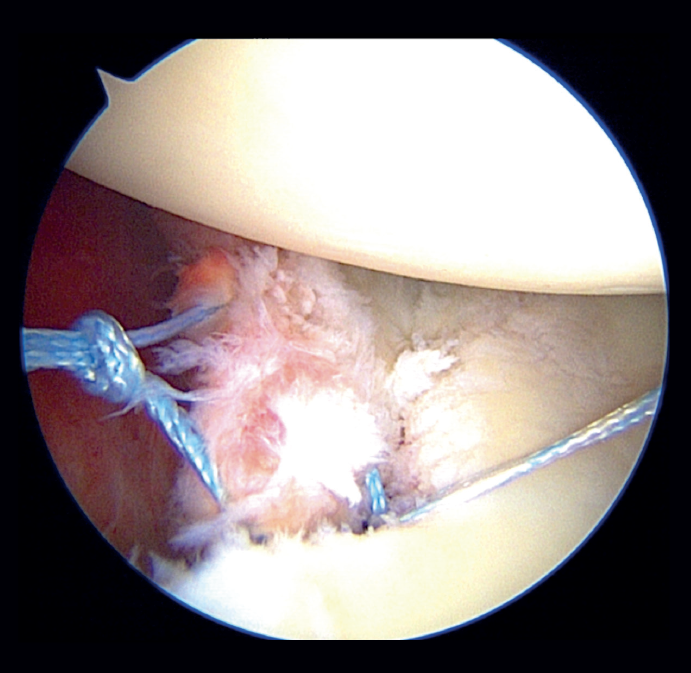

In the modified double-row/double pulley technique, and in addition to the measures commented above, an anchoring was added between the first implant and the second, at the height of half of the fractured bone fragment but in a position medial with respect to the chondral margin of the glenoid cavity (Figure 5). In this case, both the extremities crossed through the capsule at the level of half of the fragment and anterior to the latter at different points, followed by knotting and maintaining reduction of the bone fragment (Figure 6). One of the extremities of the suture knot made was tied to one of the extremities of the lower anchoring, while the other was tied to one of the extremities of the upper anchoring, thereby completing the repair procedure (Figure 7).